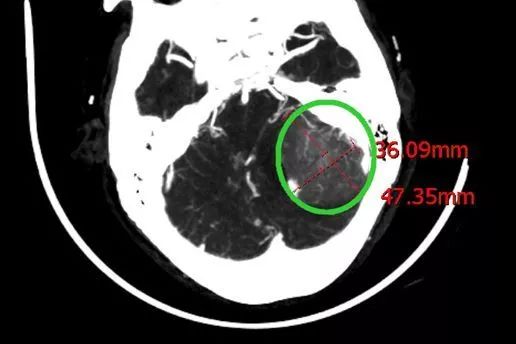

陈阿婆1月前出现头晕头痛,行走不稳、呕吐现象,到我院就诊时,神经外科专家为其做了一系列检查。经头部CT检查扫描,显示陈阿婆左侧颞骨岩部下有一个占位性的东西,大小为4.5*5CM,近似一个鸡蛋大小,患脑膜瘤的可能性较大,需要尽快手术切除。

经手术后一系列治疗及精心护理,患者恢复良好,生命体征平稳,神志清,精神可,应答正确,口齿清楚,肢体配合动作准确,术后CT复查脑肿瘤已完全消失。